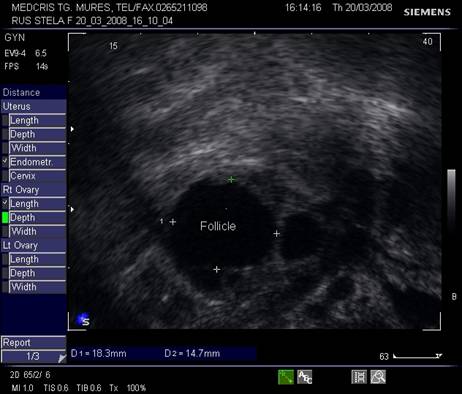

Dupa ziua a 5-7, un folicul ovarian devine dominant , fata de ceilalti ce devin atretici. In ziua 10 -a - 11-a foliculul depaseste 12 mm diametru. Cresterea foliculara de 2 - 3 mm/zi ne duce la un folicul preovulator de cca 21 mm diametru (24 - 26 mm). Doi foliculi dominanti au fost identificati in 10% din ciclurile spontane [8].

Deoarece foliculii sunt ovoidali, diametrul mediu conteaza pentru foliculometria, dupa masurarea a 3 diametre si impartirea la 3.[6]

Fig. nr.371. Folicul selectat ziua a XI a de ciclu menstrual, la ecografia transvaginala

Fig. nr.372. Folicul preovulator , in care se remarca

cumulus oophorus ( sageata, eco transv.)